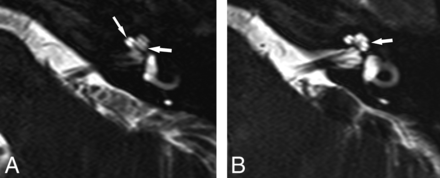

Axial 3D T2-weighted images from inferior to superior showing a normal osseous spiral lamina and interscalar septum. A, A normal osseous spiral lamina separating the scala tympani (posterior) and scala vestibuli (anterior) of the basal (anterior arrow) and middle turns (posterior arrow). B, A normal lateral R2 notch (arrow) associated with the second part of the interscalar septum between the upper basal and upper middle turns of the cochlea.

Anatomically, the continuous osseous spiral lamina separates the cochlea into 2 visible perilymph-containing chambers on MR imaging, the scala tympani and scala vestibuli, with the intervening endolymph-containing scala media not currently demonstrable on imaging. Imaging may demonstrate scalar defects and/or scalar asymmetry with enlargement of the scala vestibuli, which may be seen in association with cochlear malformations. While scala communis can be associated with scalar asymmetry, it is a more extensive malformation that results from a defect of the osseous interscalar septum, which separates the cochlear turns. This is a continuous structure that spans the entire length of the cochlea and results in a continuous ridge along the outer margin, separating it into 3 distinct turns, resulting in 3 distinct indentations or ridges along the margins of the cochlea. The second interscalar ridge (R2) or notch, associated with the interscalar septum and located along the lateral margin of the cochlea, is most easily appreciated on imaging (Fig 1).3,4